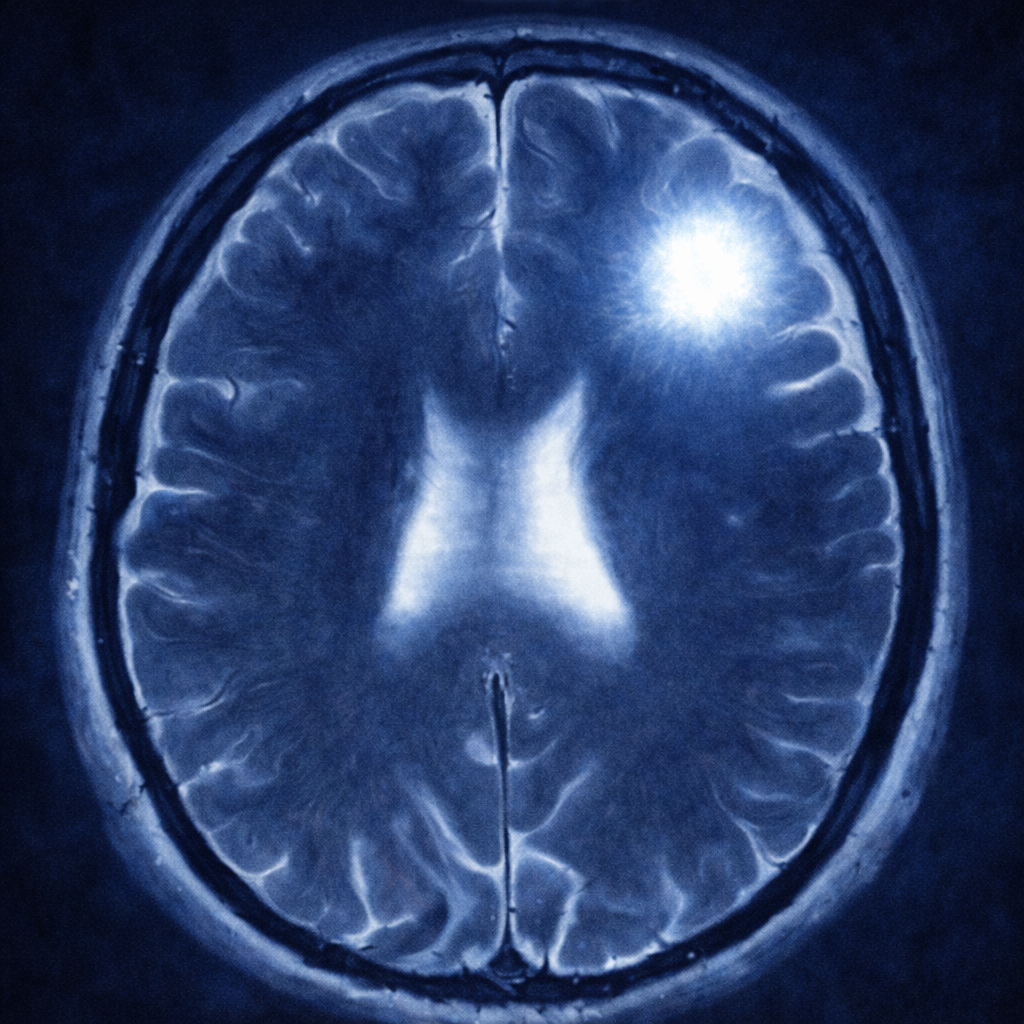

La resonancia magnética es el estudio inicial para la evaluación preoperatoria de un astrocitoma. Este estudio podrá analizar tanto la localización como las características del tumor. Dentro de las características más importantes están evaluar si capta o no el medio de contraste y qué tanta inflamación produce en los tejidos vecinos. Sin embargo, el diagnóstico definitivo de un astrocitoma se da, únicamente, a través de una biopsia con un análisis histopatológico, inmunohistoquímico y molecular. Es decir, el diagnóstico se puede establecer solamente con cirugía.